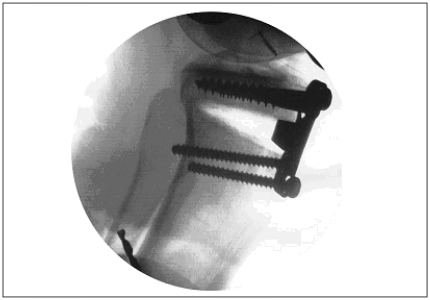

Anterior opening wedge osteotomy

The posterior slope of the tibia was increased via an opening wedge anterior HTO and fixed with a 5-mm or 10-mm buttress plate (Opening Wedge Osteotomy Plates; Arthrex Inc.), as per the randomized study design. Standard surgical protocols and instruments were used to perform the opening wedge osteotomy as recommended by the plate manufacturer. A longitudinal incision was made along the medial border of the patellar tendon. The tibial tuberosity was not detached, and the peripheral capsuloligamentous structures attached to the epiphysis were left undisturbed. The osteotomy began about 3–4 cm distal to the joint line just above the tibial tuberosity. The cut was performed using an oscillating saw and was directed slightly superior to finish distal to the PCL and capsular insertion and level with the proximal tibiofibular joint. The osteotomy was then carefully distracted open against the posterior cortical hinge. A 5-mm or 10-mm 4-hole HTO plate was positioned and rigidly fixed along the medial side of the patellar tendon. We used lateral fluoroscopic images to confirm the adequacy of positioning of the hardware as well as the presence of an intact posterior cortex (Fig. 3). After the osteotomy and plating intervention, we also used the lateral knee fluoroscopic images to measure posterior tibial slope.7 The experimental protocol was repeated for each of the 6 cadaveric knee specimens.

Fig. 3.

Lateral fluoroscopic view of and anterior osteotomy with a 10-mm opening wedge plate.